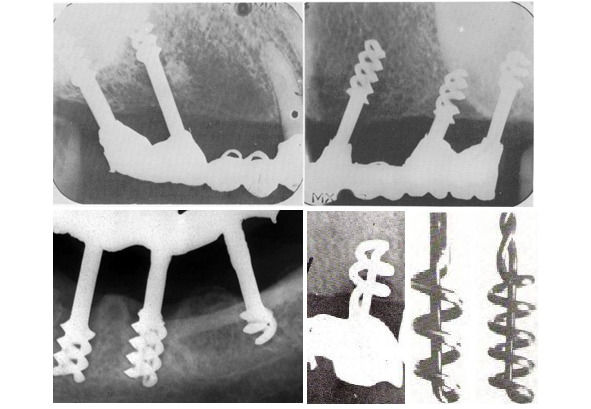

Одним из направлений эволюционного развития формы имплантата можно считать игольчатый имплантат.

Игольчатый имплантат предложили Д-р Шершеве (Chercheve) и д-р Скайлом (Scialom) 1940—1980 гг

Конечно при разработки данного вида опоры не было соблюдения понятий биофизики и биомеханики поведения имплантата в костной ткани. Да и сама биомеханика, как наука только закладывалась.

Игольчатый имплантат смог обеспечить неподвижную опору в полости рта. И как этап эволюции его заслуга не подлежит сомнению.

Такие опоры не долговечны, но достаточно легко заменимы. Надежность ортопедической конструкции обеспечивается значительным количеством опор.

Следующим шагом в эволюции можно считать спиралевидные имплантаты. Грубо говоря игольчатому имплантату придали форму спирали для увеличения площади соприкосновения с костной тканью. Такое увеличение площади привело к большей стабильности имплантатов в костной ткани.

Д-р Шершеве (Chercheve) и д-р Скайлом (Scialom) 1940—1980 гг, а так же д-р Формиджини (Formiggini) начали применять спиральные имплантаты

Спиралевидный имплантат – начало эры современной дентальной имплантации.